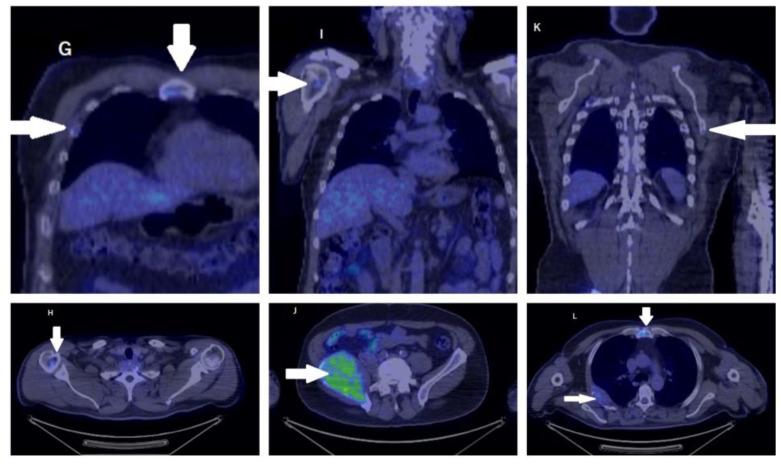

Developing in a limited space, rare tumors located at the nose and paranasal sinuses are sometimes difficult to diagnose due to their modest clinical presentation, which is uncorrelated with anatomopathological diversity. This limits the preoperative diagnosis without added immune histochemical study; for that reason, we present our experience with these tumors with the intention of raising awareness. The patient included in our study was investigated by our department through clinical and endoscopic examination, imaging investigations, and an anatomic-pathological study. The selected patient gave consent for participation and inclusion in this research study in compliance with the 1964 Declaration of Helsinki.

在有限的空间中发育,由于其临床表现温和,与解剖病理学多样性无关,位于鼻腔和鼻旁窦的罕见肿瘤有时难以诊断。这限制了没有额外免疫组织化学研究的术前诊断;因此,我们介绍了我们在这些肿瘤方面的经验,旨在提高认识。我们科室通过临床和内镜检查、影像学检查以及解剖病理学研究对纳入研究的患者进行了调查。所选患者同意参与并符合 1964 年赫尔辛基宣言纳入本研究。